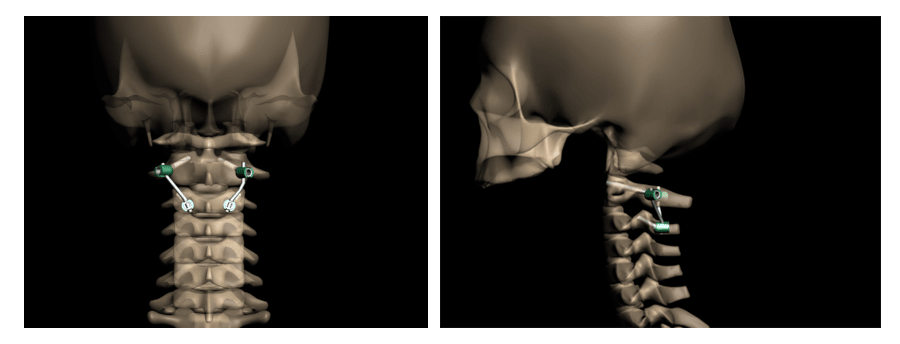

Рис.3 Схема репозиции и фиксации позвонков при переломе палача